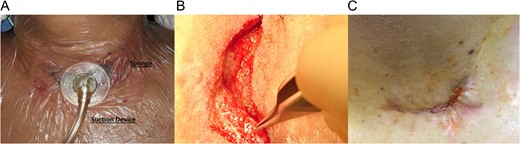

Partial opening of the cervical wound was done, and necrotic tissue debridement with extensive irrigation of the wound with saline and iodine over the cervical esophagus was performed. After this to protect the esophago-colonic anastomosis from direct contact with the V.A.C. a small paraffin gauze dressing (Lomatuell H, Paraffin Gauze Dressing) was placed over the cervical esophagus. The V.A.C. sponge was fashioned to fit the wound and placed over it. The adhesive drape was fixed to the neck skin and continuous suction between 100 and 125 mmHg was installed (Fig. 2A). In the first week, V.A.C. system drained about 50cc of saliva-like fluid daily and was changed every 2 days, once granulation tissue had begun to form over the wound, the system was changed every 5 days and no paraffin gauze was used (Fig. 2B). All V.A.C. changes were done in the operating room and during the first week of V.A.C. treatment, patient received total parental nutrition, on the 10th day patient was able to ingest liquids. Twelve days after initial use, the leak closed, since no fluid came out of the V.A.C. system, and after the patient resumed full normal diet, she was discharged home. On follow-up controls, the patient was in good condition (Fig. 2C).

(A) Functional V.A.C. system in-patient. (B) Granulation tissue in the cervical wound. (C) Wound after therapy.